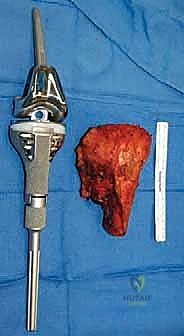

جوهر العملية: تصميم الأطراف الاصطناعية الداخلية المعيارية

كانت الزرعات المبكرة، على الرغم من كونها ثورية، تعاني غالباً من عيوب في التصميم وأخطاء في التصنيع، مما أدى إلى كسرها أو ارتخائها. أما اليوم، فقد تغير المشهد تماماً بفضل الأنظمة المعيارية (Modular Systems).

ما هي الأطراف الاصطناعية الداخلية المعيارية؟

بدلاً من انتظار أسابيع لتصنيع مفصل مخصص لكل مريض، تأتي الأنظمة الحديثة على شكل قطع متعددة الأحجام والأطوال (مثل قطع الليغو). يمتلك الأستاذ الدكتور محمد هطيف في غرفة العمليات مجموعة كاملة من هذه القطع:

* السيقان (Stems): التي تُغرس داخل القناة النخاعية للعظم المتبقي السليم.

* الأجزاء البينية (Intercalary segments): لتعويض طول العظم المفقود (سواء كان 5 سم أو 20 سم).

* المفاصل (Joint mechanisms): مفاصل ركبة أو كتف أو ورك صناعية متطورة تسمح بالحركة.

هذه المعيارية تمنح الجراح مرونة هائلة. إذا اكتشف الجراح أثناء العملية أن الورم يمتد أكثر مما أظهرته الأشعة، يمكنه ببساطة استئصال المزيد من العظم واستخدام قطعة تعويضية أطول في نفس اللحظة.

1. استئصال الورم بهوامش أورام مناسبة (Tumor Resection)

هذا أمر غير قابل للتفاوض. الهدف الأساسي دائماً هو الإزالة الكاملة للورم بكتلة واحدة (En bloc resection) مع تغليفه بطبقة من الأنسجة السليمة (العضلات والدهون) لضمان عدم تسرب أي خلية سرطانية إلى الجرح.